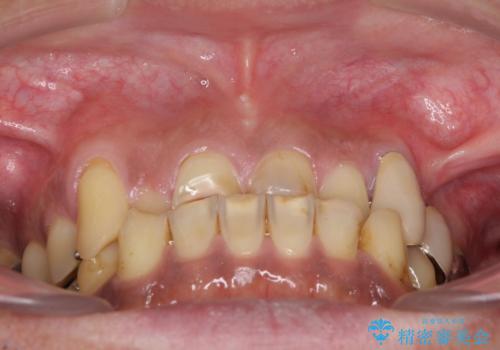

- すり減った前歯や奥歯の銀歯を気にして来院された患者様です。

骨格的な反対咬合により上顎前歯の先端が顕著にすり減っている状態でした。

奥歯の欠損が散見されており、銀歯の装着されている歯も多いため、ワイヤー矯正にて歯列を調整し、その後オールセラミッククラウンにて補綴治療を行うこととしました。

反対咬合改善には奥歯の咬み合わせをしっかりと改善させることが必要となりますが、奥歯に欠損が多いため、矯正治療が難航することが予想されます。